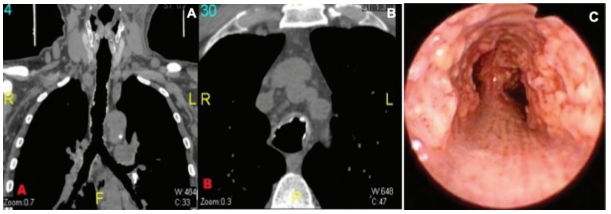

(2)骨化性气管支气管病 :指气管、支气管黏膜下有多发性骨质或软骨组织结节状增生并突向管腔的良性病变 ,结节表面覆盖薄层正常气管黏膜。该病主要与树枝型肺骨化鉴别,前者病变位于较大气道,后者骨化灶位于终末气管的周围,且不形成突向管腔的结节。